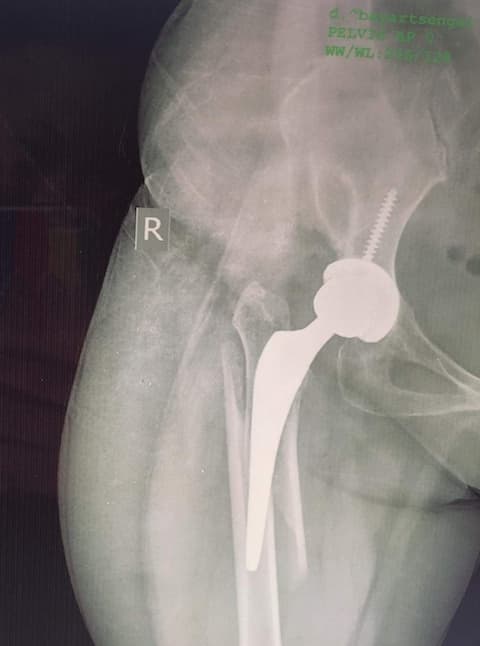

Periprosthetic fracture-Хиймэл үе суулгасны дараах хугарал

Хугарал засах мэс засал image10Хугарал засах мэс засал image11

Өвчтөн Б 52 настаЙ эмэгтэй 2020 оны 04 сард дунд чөмөгний хүзүүний эмгэг хугаралын улмаас түнхний үеийг бүтэн солих мэс засал хийлгэсэн. Мэс заслын дараах 25 дах хоног дээр явганаас халтирч унаж дахин хугаралыг зассан үеийн рентген зураг